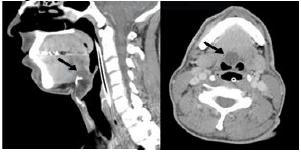

Analise as imagens de tomografia computadorizada a abaixo e assinale a alternativa que melhor representa o diagnóstico.